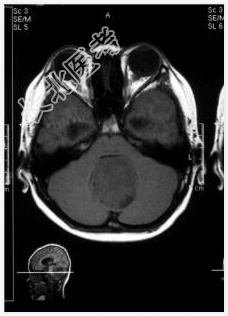

- [材料题] 患者,男性,10岁,因头晕、头疼伴呕吐1月,加重2天入院。做头颅MRI检查。

- 简答题1、诊断及依据是什么?

- 简答题2、鉴别诊断有哪些?